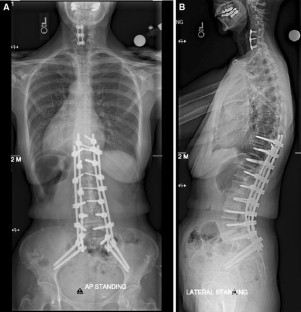

Sacropelvic fixation should be considered in any patient with a long construct ending in the sacrum, those patients with associated risk factors for loss of distal fixation or high risk for pseudarthrosis at L5–S1, and those undergoing three column osteotomies or vertebral body resections in the low lumbar spine. Current pelvic fixation techniques with iliac screws, multiple screw/rod constructs, and S2-alar-iliac screws are all viable techniques for achieving pelvic fixation.

There is growing evidence that pelvic fixation may become the standard for obtaining long fusions in adult scoliosis. Although technically challenging, in selected cases the use of four pelvic screws and/or four rods across the lumbosacral pelvis can help address pseudarthroses, implant breakage, and screw pullout secondary to osteoporosis. Ultimately, indications and techniques should be individualized to the patient and based on surgeon preference and experience.